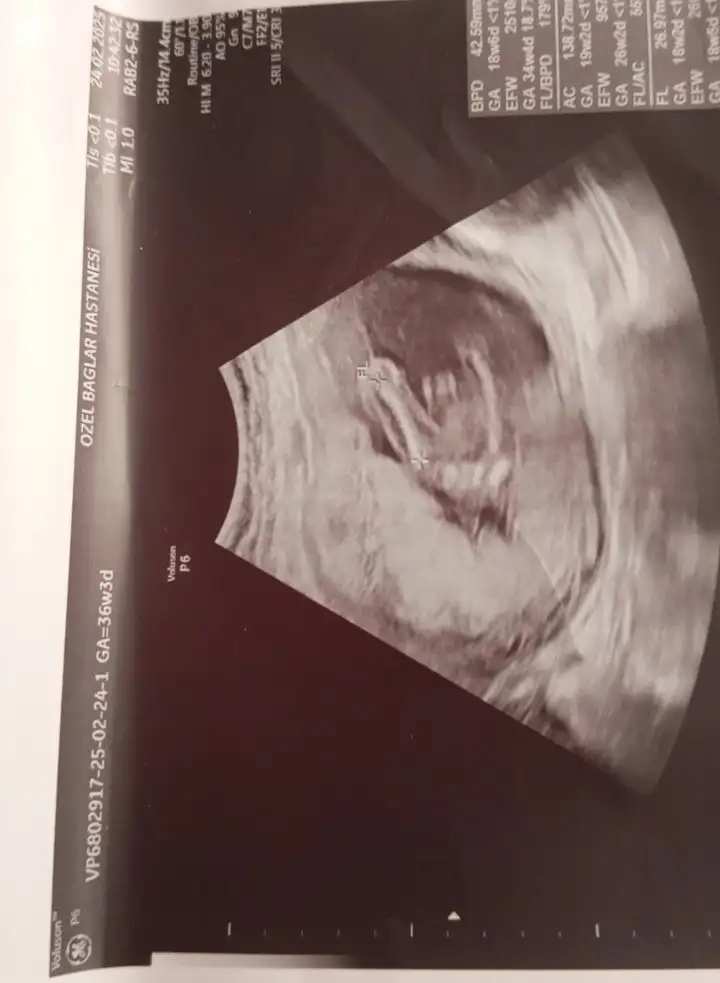

Erkek hissettimKızlar 10 haftalık hamileyim cinsiyet tahmini sizce nedir

Erkekmiş

Hayırlı olsun canımErkekmiş

Kızlar tahmininiz nedir

Fotolar doktor taarafından hiç güzel çekilmmemişKızlar tahmininiz nedir

Yarın kontrolüm var yeniden atarım bide özelde çekildi yani bu kadar kalitesiz olurmu ya yarın devletinki basıl olucak bakalımFotolar doktor taarafından hiç güzel çekilmmemiş

Ama kalp atış hızı erkeki gösteriyor keseyi tam çözemedim şekli beli olmamış fasulye olursa erkek yuvarlak olursü kız olur genelde

Fotolar doktor taarafından hiç güzel çekilmmemiş

Evet özeller gerçekten güzel çekmiyor tamambeklilorimYarın kontrolüm var yeniden atarım bide özelde çekildi yani bu kadar kalitesiz olurmu ya yarın devletinki basıl olucak bakalım